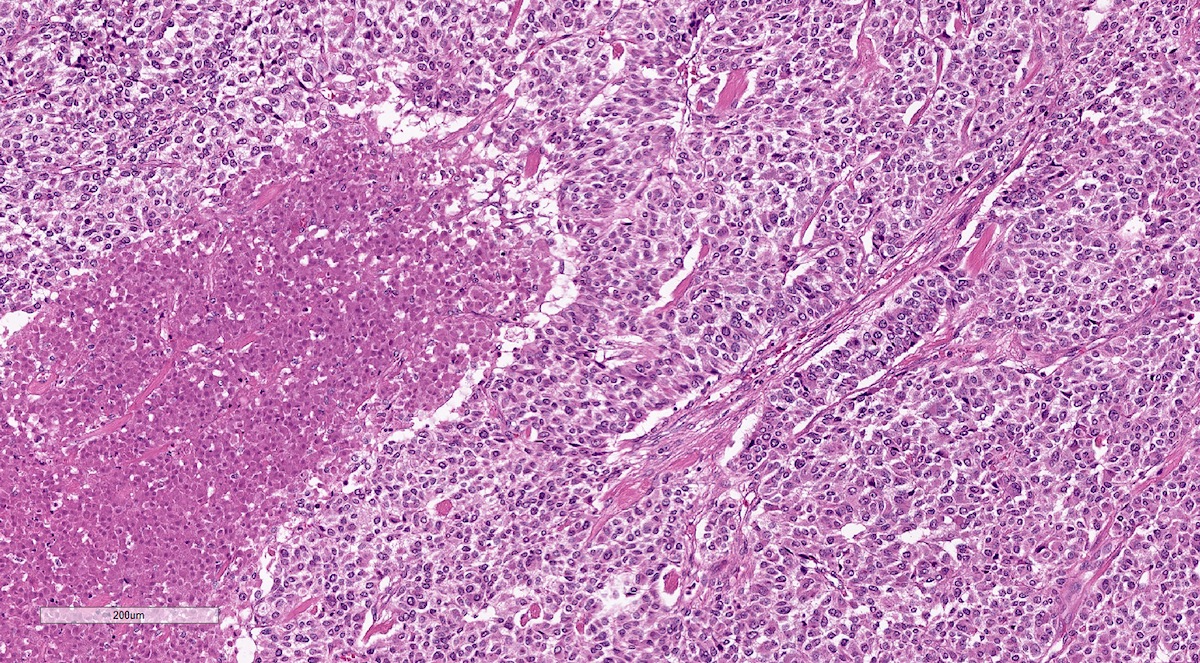

Microscopic (histologic) description

- Prevailing histologic pattern: epithelioid chief cells arranged in distinctive clusters / nests (zellballen pattern), separated by prominent fibrovascular stroma (J Clin Med 2018;7:280)

- Trabecular pattern: ribbons or cords of epithelioid cells divided by fibrous bands

- Other patterns: pseudorosette, angioma-like, spindled and sclerosing

- May have dysmorphic vessels, melanin-like pigment (neuromelanin) (pigmented paraganglioma), amyloid, abundant stroma and osseous metaplasia (Diagn Pathol 2012;7:77, Hum Pathol 1992;23:33)

- Special histopathologic features usually related to genetic syndromes:

- VHL syndrome: prominent stromal edema, clear cytoplasm and lipid degeneration (Am J Surg Pathol 1987;11:480)

- SDHx related syndrome: granular eosinophilic cytoplasm (Am J Surg Pathol 2020;44:422)

- MEN2 syndrome: unilateral or bilateral adrenal medullary hyperplasia (Neoplasia 2014;16:868)

Microscopic (histologic) images

Contributed by Luvy Delfin, M.D. and Sylvia L. Asa, M.D., Ph.D.